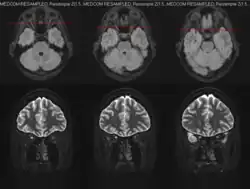

Para el diagnóstico pueden ser necesarios diferentes procedimientos, como una valoración oftalmológica completa, con examen de la agudeza visual y la capacidad de visión de colores. También se realizan una observación del fondo de ojo mediante oftalmoscopia y estudios como la resonancia magnética cerebral.